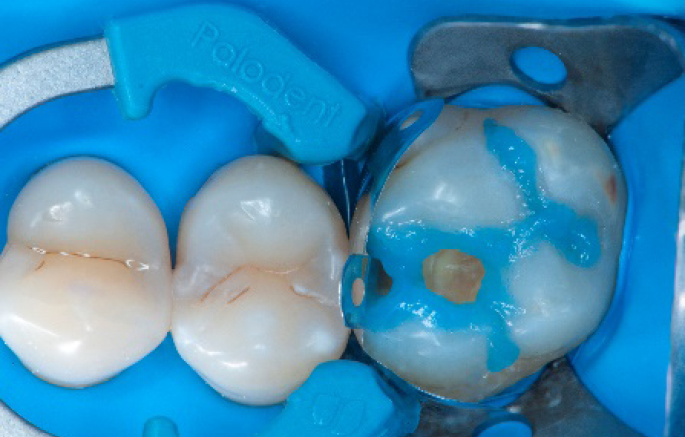

Step 1:

The situation after rubber dam isolation.

Step 4:

The complete Palodent1 system in place: sectional matrix, wedge and ring.

Step 8:

Transformation of class II into class I, restoring the interproximal wall with Spectra ST4 composite in shade A2.